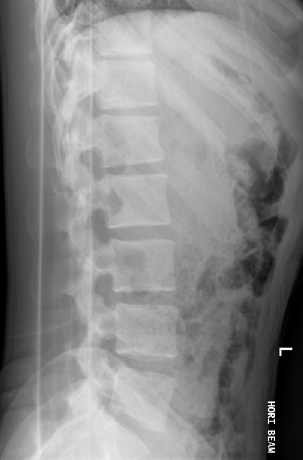

With all this talk about sandwiches, it’s helpful to compare a fresh “ham and cheese on rye” to one with “heavy mileage” to really understand the flavor of what we’re discussing. Since a picture is worth a thousand words, we’ll use some visual support to drive this sandwich point home. Even without experience reading X-rays, it’s easy to see which of these two spines would feel better playing golf, pickleball, or planting the garden.

For some proof, let’s take a look at the X-ray with the numbering. Focus on the segment labeled L4-L5 and notice how little space remains between those vertebrae. That tight gap signals advanced degeneration and a spine under constant stress. It is a severe degenerative condition, and there is not much “gold” there! Look one level higher in the degenerative spine and you’ll see additional disc loss. At L2, the vertebra has shifted forward on L3, adding another layer of strain the body must manage.

Now compare it to the second X-ray. The difference is clear. There’s visible space between the vertebrae, that is a spine that has not been sandwiched!